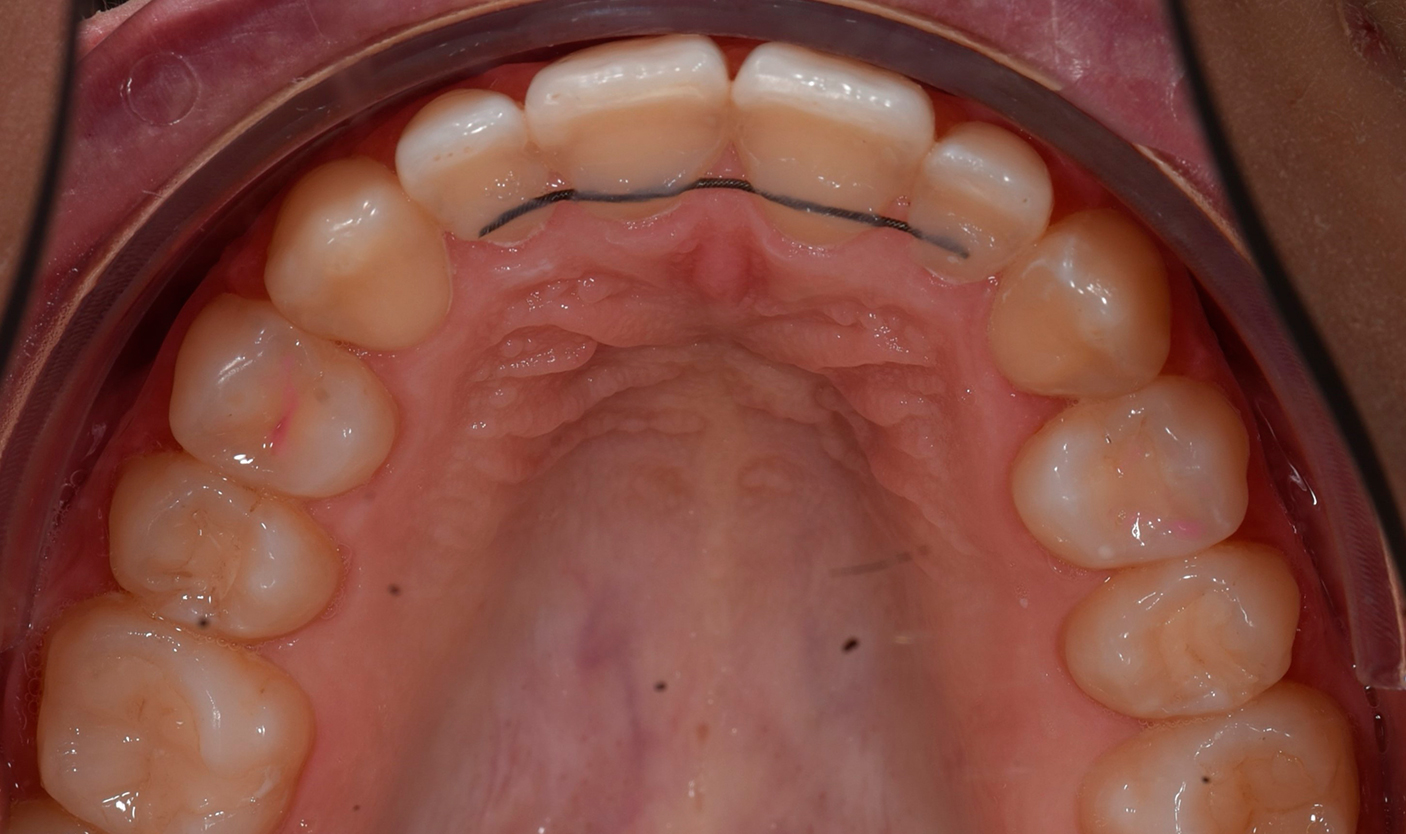

- несъемные – устанавливает ортодонт для круглосуточного непрерывного ношения. Аппарат фиксирует 6-8 передних зубов. Представляет собой металлическую дугу, закрепляемую с лингвальной (внутренней) стороны зубного ряда;

Фото до и после лечения

Наши работы

Фотогалерея